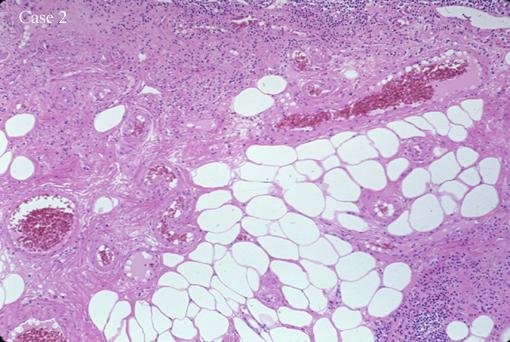

Two cases of angiolipoma which were removed endoscopically.

Non-epithelial tumors/Angiolipoma

Histology